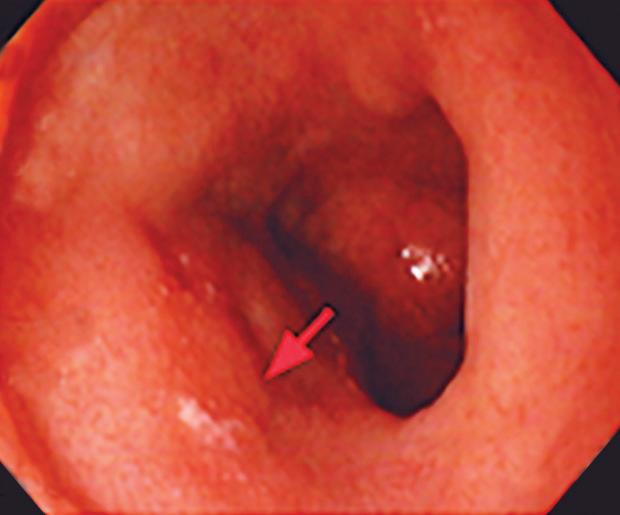

CASOS CLÍNICOS Biopsia guiada por ecoendoscopía como herramienta diagnóstica mínimamente invasiva para metástasis mesorrectal de carcinoma de células claras renales: reporte de caso

Nicole Marie Kahn, Mayra Florencia Defanti, Yanina Gabriela Carlino

CASE REPORTS Endoscopic Ultrasound-Guided Biopsy as a Minimally Invasive Diagnostic Tool for Mesorectal Metastasis From Clear Cell Renal Carcinoma: A Case Report